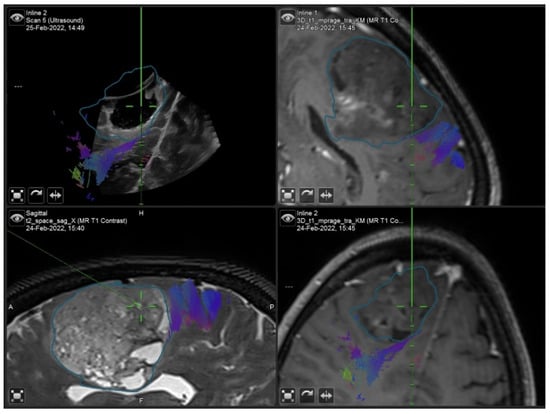

3.1.2. Case 2

3.1.3. Case 3